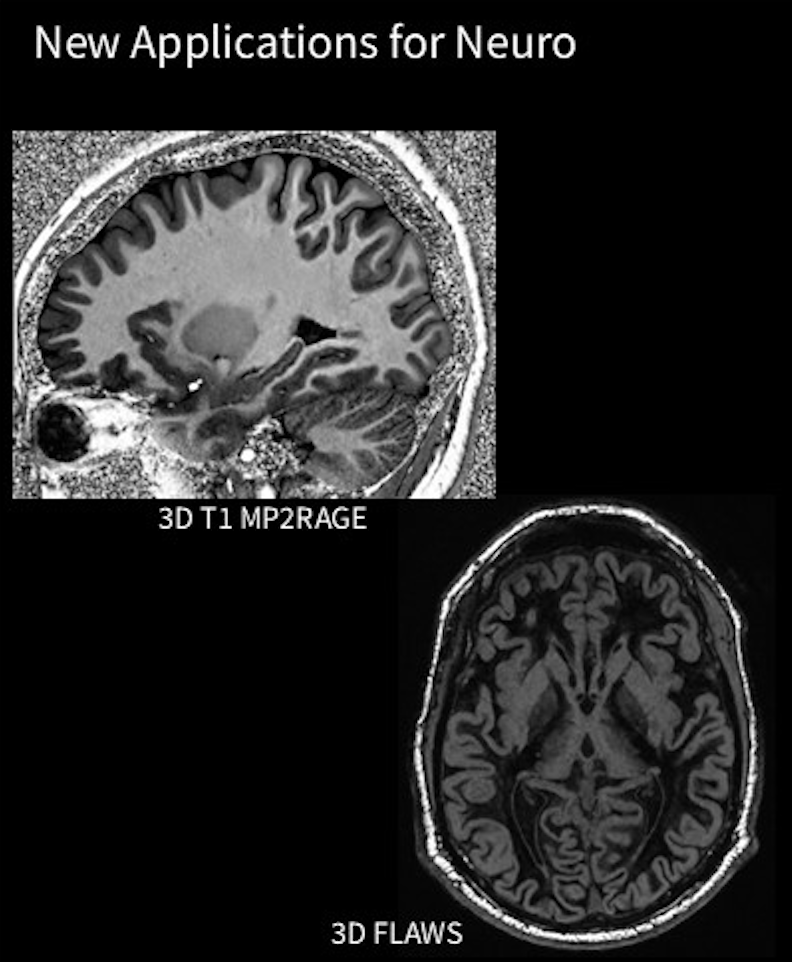

GE装置でも3D T1 MP2RAGEシーケンス、3D FLAWSシーケンスが使用可能となりました。3D FLAWSとは、SPGR系のdouble IRシーケンスです。この2つにもdeep learningが使用できるため、短時間で撮影できます。